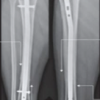

The aims and objectives of the study are to determine the functional and radiological outcome after operative management of supracondylar fracture humerus in children by assessing pain, elbow ROM, carrying angle, Baumann angle, fracture union, and complications. Primary outcome is based on Baumann angle, carrying angle, ROM at elbow, Flynn criteria and disabilities of the arm, shoulder, and hand (DASH) score. Secondary outcome fracture union, complication and compare between closed reduction and percutaneous pinning (CRPP) and Image 1.

The study was conducted on pediatric patients with supracondylar fractures of the humerus, admitted to the Department of Orthopaedics at Lala Lajpat Rai Hospital and Ganesh Shankar Vidyarthi Memorial Medical College in period of November 2022–July 2024 and was designed as a prospective study with inclusion criteria – Age: 2–16 years, both sexes, skeletally immature patients, modified Gartland’s type II, type III, and type IV fractures and exclusion criteria -Intra-articular fractures of the lower end of the humerus, flexion-type supracondylar fractures, fractures in children over 16 years of age, neuromuscular and metabolic disorders, polytrauma patients, compound fractures. The study included 53 pediatric patients who met the inclusion and exclusion criteria. Upon admission, each patient underwent a detailed examination following hemodynamic stabilization. Standard anteroposterior and lateral view X-rays were taken to classify fractures using the modified Gartland classification. Emergency management involved providing general supportive measures, examining associated injuries, and immobilizing the elbow with a long arm splint in 30–40° of flexion using a Plaster of Paris (POP) slab. The affected limb was elevated to reduce swelling, and active and passive movements of the fingers were encouraged. Ice fomentation was applied in cases of swelling, and analgesics were administered for pain control. Preoperative go thorough physical examination, focusing on assessing the neurovascular status beyond the fracture site, signs of compartment syndrome, radial pulse, and nail bed circulation. Initial management included try closed reduction and application of an above-elbow posterior POP slab with the elbow flexed at 90°, and the affected limb was elevated to minimize swelling. Patients were scheduled for surgery after written informed consent was obtained from the child’s parents or guardians. In cases of closed reduction with K-wire fixation, antibiotics were discontinued after 3 days. For open reduction procedures, intravenous antibiotics were given for 5 days, followed by oral antibiotics until suture removal. Closed reduction method included biaxial longitudinal traction, fracture site correction, and checking radial pulse. Reduction adequacy was verified with an image intensifier, and satisfactory alignment led to either plaster slab application or K-wire fixation. Open reduction was performed for unsuccessful closed reductions. Post-operative included post-surgery limb elevation, finger movement encouragement, close observation for compartment syndrome, dressing changes, X-rays, and K-wires were removed between 4 and 6-week post-surgery. Follow-up appointments assessed clinical and radiological outcomes, using Flynn criteria and modified DASH score at 12 weeks.